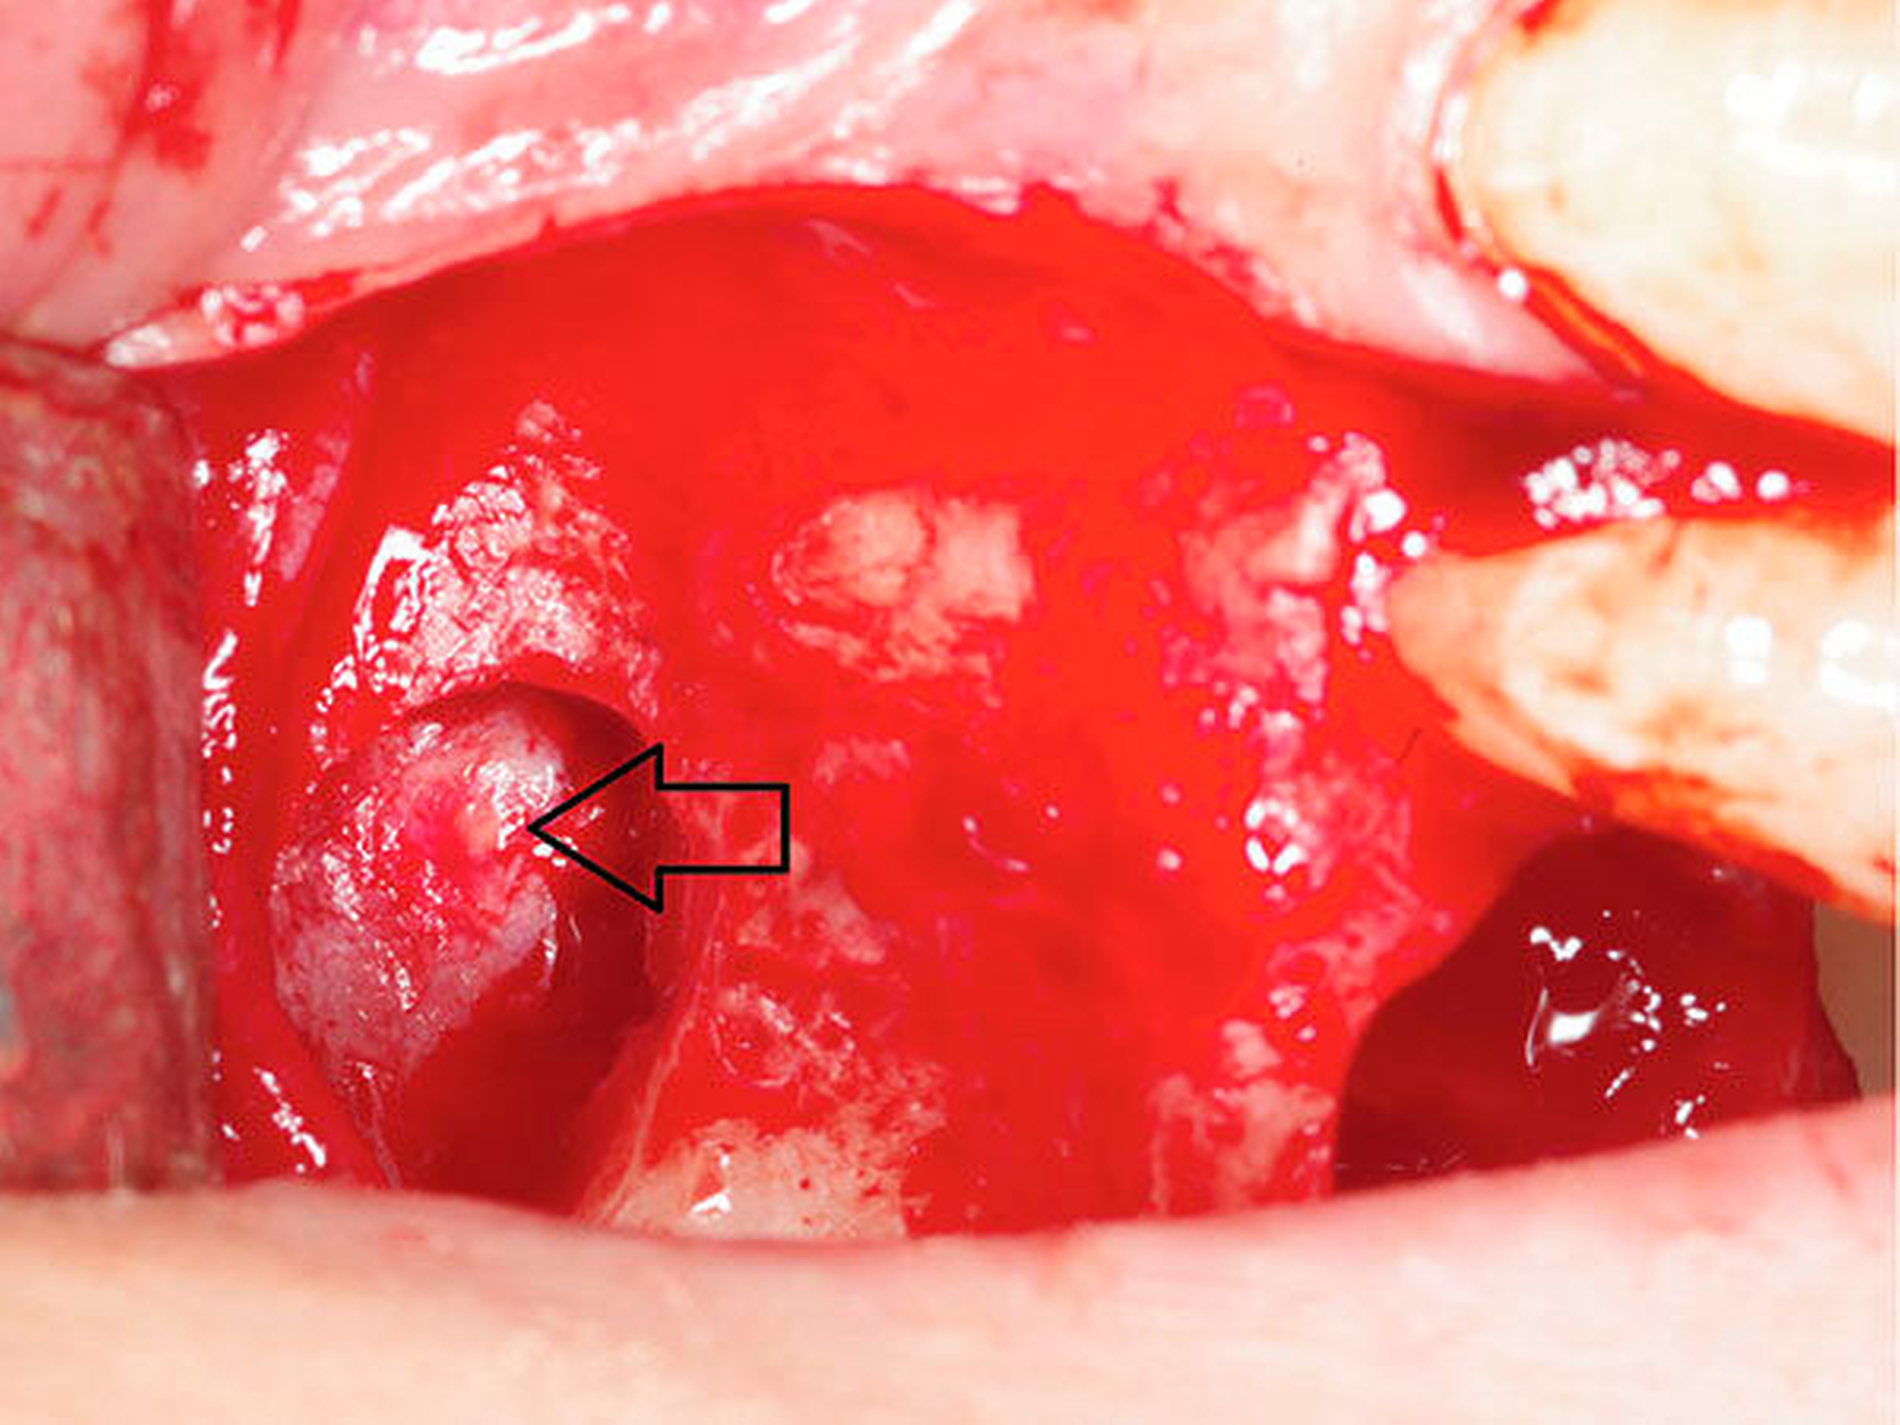

Nach Entfernung des Knochens wurde bereits der durch die Kieferhöhlenschleimhaut schimmernde Fremdkörper sichtbar (Abbildung 2), der gemeinsam mit einem Teil der deutlich verdickten Schleimhaut entfernt wurde. Bei der anschließenden Inspektion der Kieferhöhle imponierte eine Ansammlung von zystischem Granulationsgewebe, das ebenfalls entfernt und zur histopathologischen Aufbereitung eingesandt wurde (Abbildung 3). Die Kieferhöhle wurde endoskopisch nach Granulationsresten untersucht und durch Spülung gereinigt. Da das Ostium naturale weit offen war, konnte auf eine Infundibulotomie verzichtet werden. Das faziale Fenster wurde mit einer resorbierbaren Membran mit langer Standzeit verschlossen, das Periost geschlitzt, Fenster und Alveole plastisch gedeckt (Abbildung 4). Der Patientin wurden zusätzlich ein orales Antibiotikum, abschwellend wirkende Nasentropfen und Analgetika rezeptiert. Überdies wurde auf ein zweiwöchiges Schneuzverbot hingewiesen. Die histopathologische Untersuchung ergab unspezifische granulomatöse Infiltrate mit ausgedehnten Nekrosen sowie septierte Hyphen im Sinne eines Aspergilloms. Der Fremdkörper entsprach wie erwartet einem Materialrest der Wurzelfüllung. Die Patientin wurde in einen engen ambulanten Recall eingebunden. Die Nahtentfernung erfolgte nach zehn Tagen. Nach drei Monaten kam die beschwerdefreie Patientin zur Kontrolle.